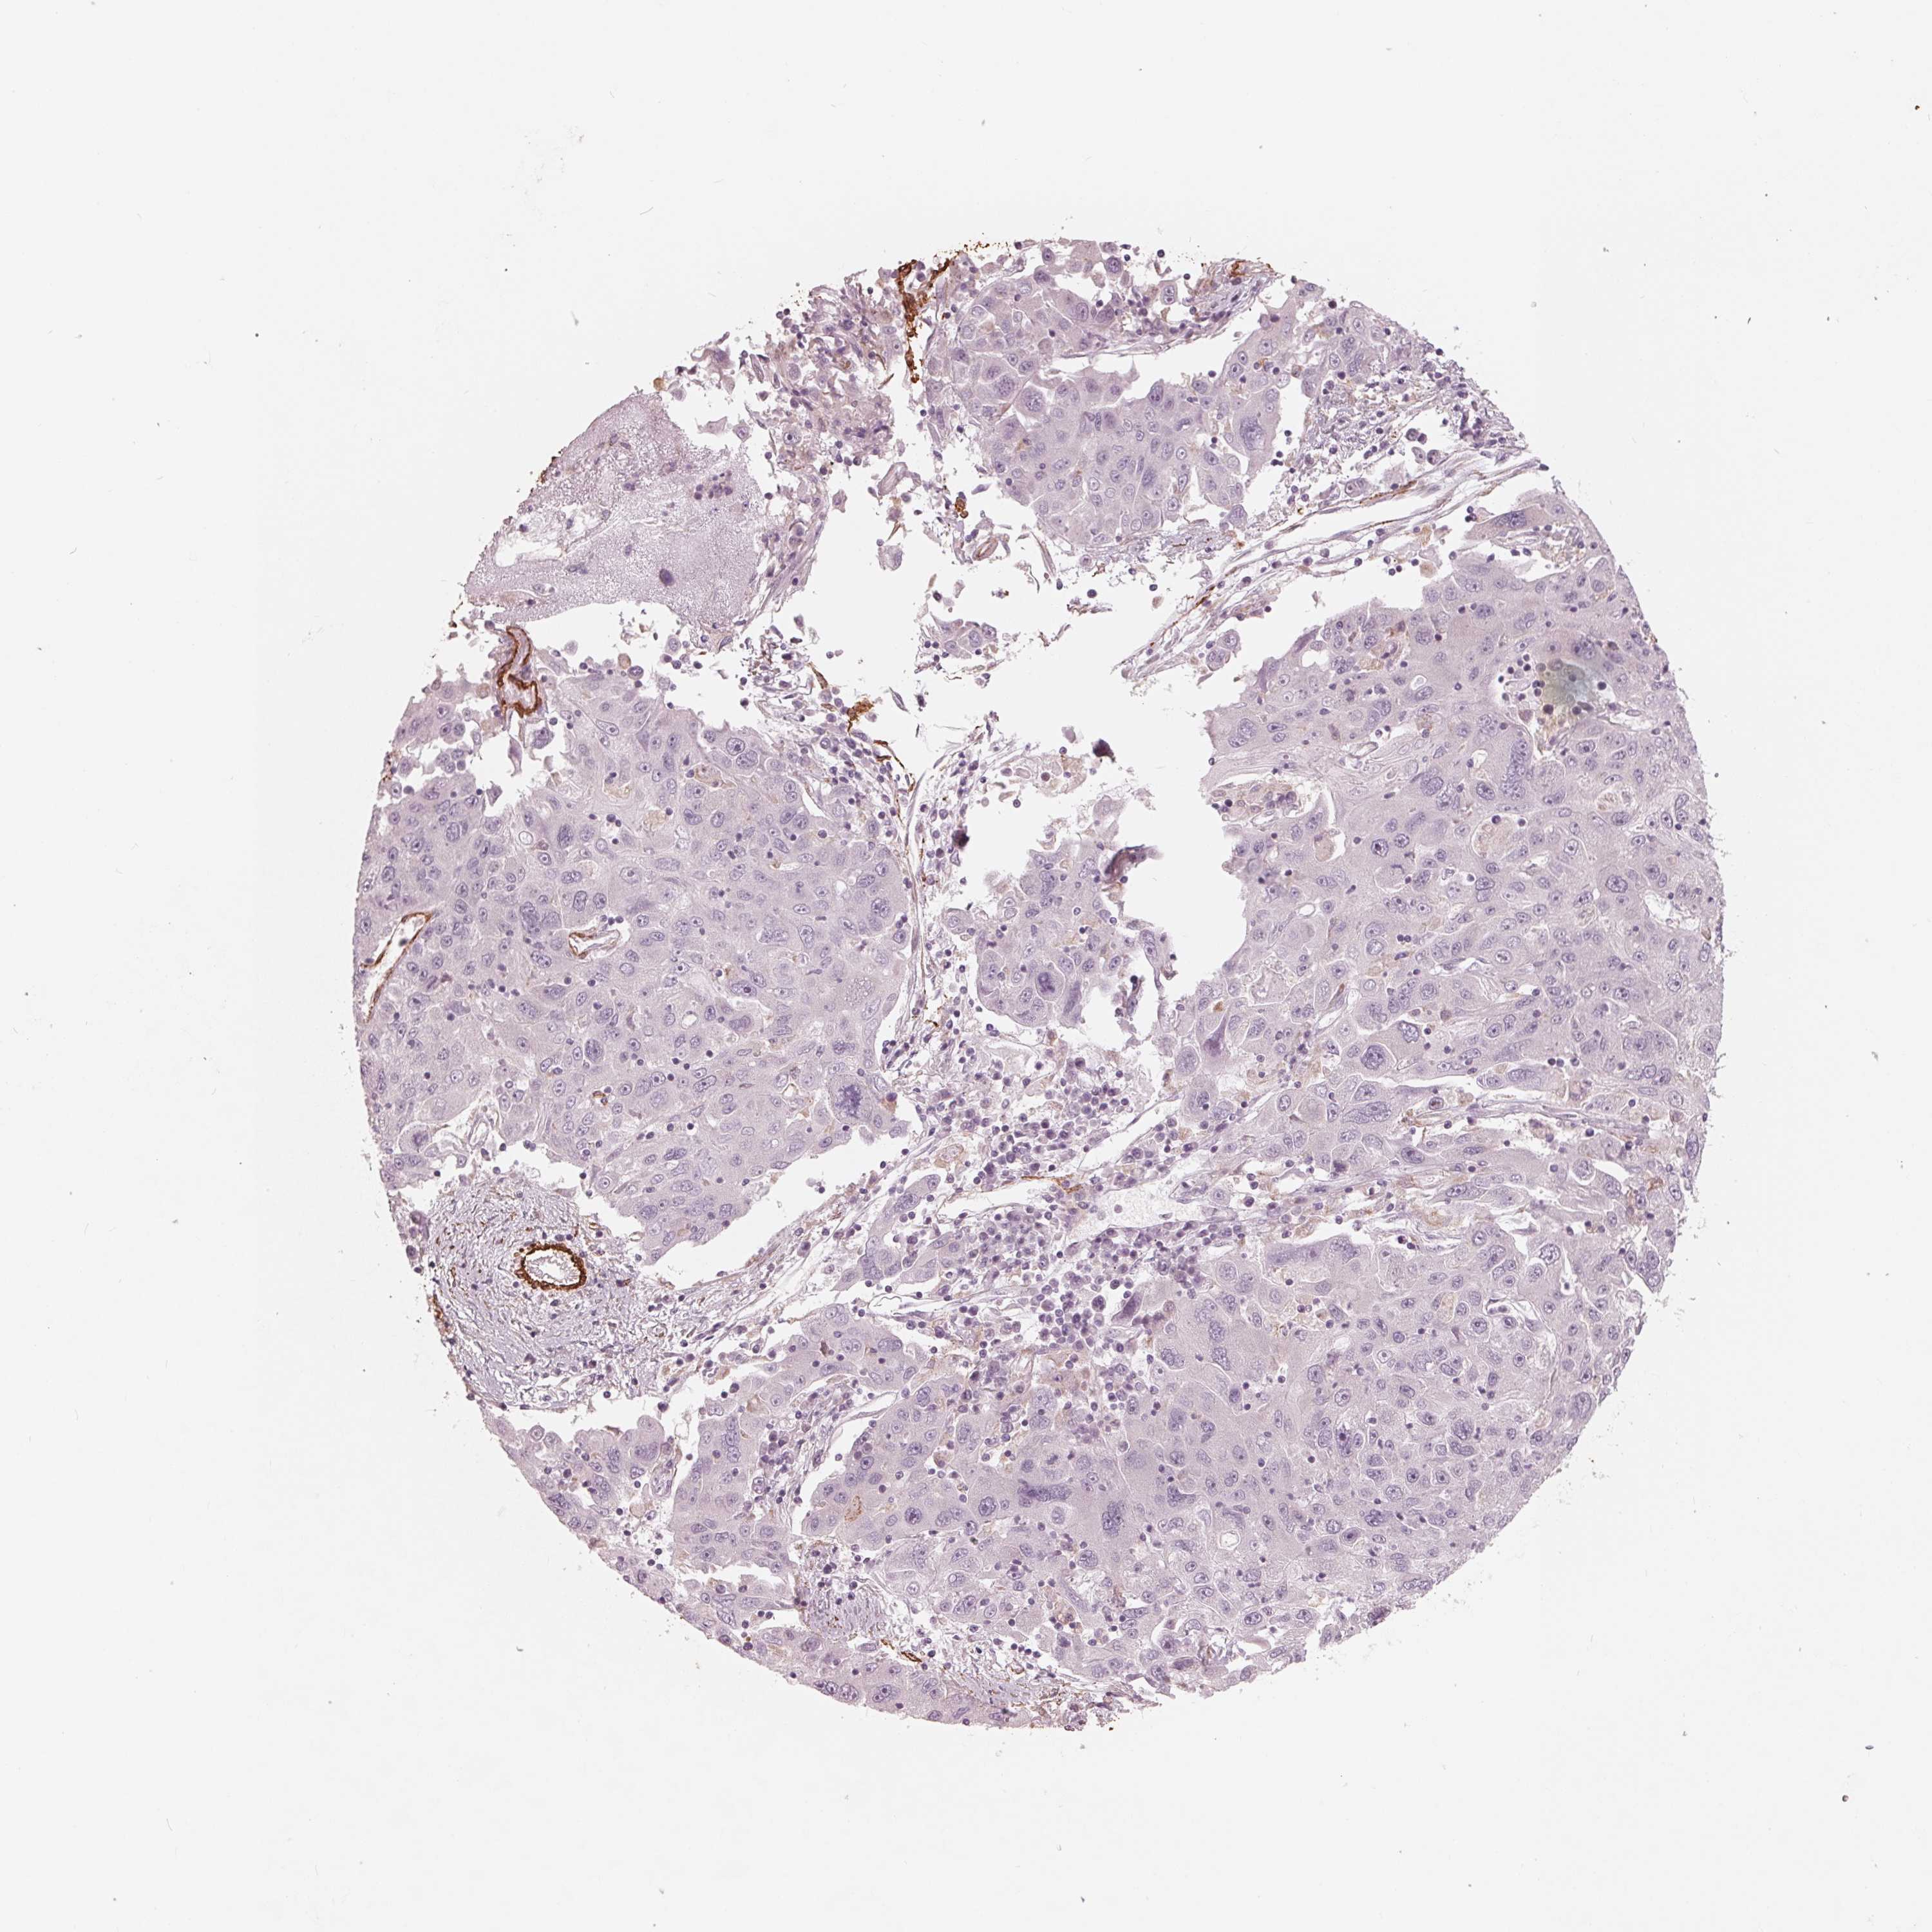

STOMACH CANCER - Protein expressioni

A mouse-over function shows sample information and annotation data. Click on an image to view it in a full screen mode. Samples can be filtered based on level of antibody staining by selecting one or several of the following categories: high, medium, low and not detected. The assay and annotation is described here.

Note that samples used for immunohistochemistry by the Human Protein Atlas do not correspond to samples in the TCGA dataset.

Antibody stainingi

Antibody staining in the annotated cell types in the current human tissue is reported as not detected, low, medium, or high, based on conventional immunohistochemistry profiling in selected tissues. This score is based on the combination of the staining intensity and fraction of stained cells.

Each image is clickable and will lead to virtual microscopy that enables deeper exploration of all samples and also displays staining intensity scores, fraction scores and subcellular localization as well as patient and tissue information for each sample.

Antibody HPA065946

Staining

High

Medium

Low

Not detected

Intensity

Strong

Moderate

Weak

Negative

Quantity

>75%

75%-25%

<25%

None

Location

Nuclear

Cytoplasmic/membranous

Cytoplasmic/membranous,nuclear

Adenocarcinoma, NOS